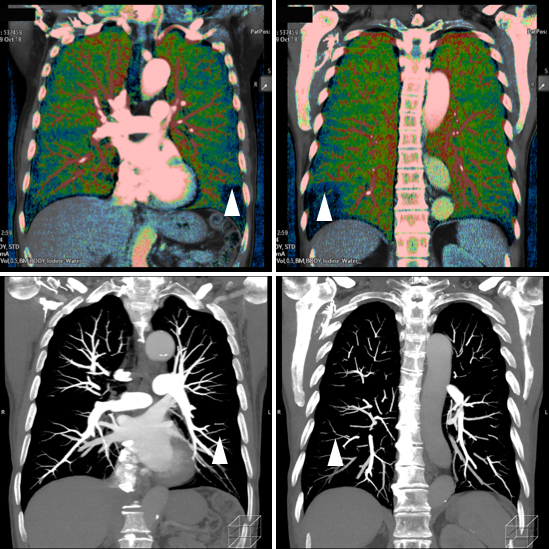

さらに、これら2台のCT装置にはdual energy システムも搭載しており、体内の物質を弁別する能力があります。特に造影剤の分布を定量的に評価可能なため、各臓器における造影剤の取り込み状況に加えて繊維化の度合いや出血との鑑別等への有用性が期待されます。また、様々なX線エネルギーをシミュレーションした画像も作成できるため、造影剤によるコントラストの向上による造影剤量の低減も可能です。

通常の画像(左:70keV)に比べ、低いエネルギーの画像では血管の描出が明瞭となっている。(中央:60keV、右:50keV)

右左両肺の下葉の肺動脈末梢に血栓性の閉塞があり(下段矢頭)、ヨードマップにて同部位の肺実質における造影剤の取り込低下が確認できます。